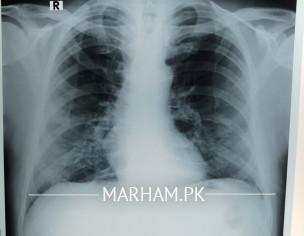

My father tested positive for corona yesterday. He has had fever 100 101, severe weakness and cough, loss of appetite etc. We got a chest extant done today and the radiologist’s report says this “â€Fibro nodulations both mid and lower zones. Rest of the lungs are clear . Cardiac size within normal limits . No evident of pleural effusion. Costophrenic angles are clear . Bony cage is intact . Conclusion. Bilateral pulmonary infection “â€. Pls advice what can be done should he be taken to the hospital?

dear the findings in x ray can be due to corona virus infection

but they can also be due to other causes

Shortness of breath no I don’t know for sure although when he speaks he starts panting and coughing after a few sentences. He’s diabetic and hypertensive both with arthritis. This is today’s xray

Can anyone pls explain what the X-ray shows? He started antibiotic on Saturday. Azomax 500 once daily with Panadol x 2 thrice a day